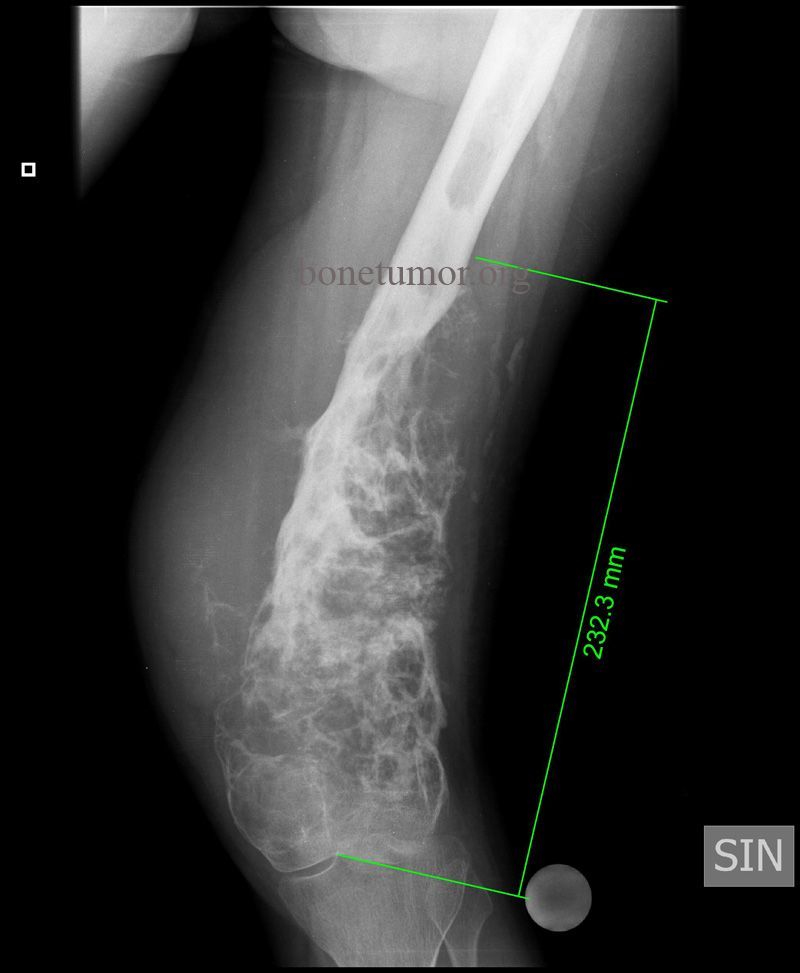

Location of osteosarcoma

Metaphysis of long bones

• Femur, tibia, humerus (56%); flat

bones, spine (older patients)

• May be polyostotic (not common)

• Hematogenous spread to lungs is

common

Describe what to expect in Xray of osteosarcoma

Infiltrative tumor… extends to soft tissues. Has malignant cells producing osteoid

Osteosarcoma